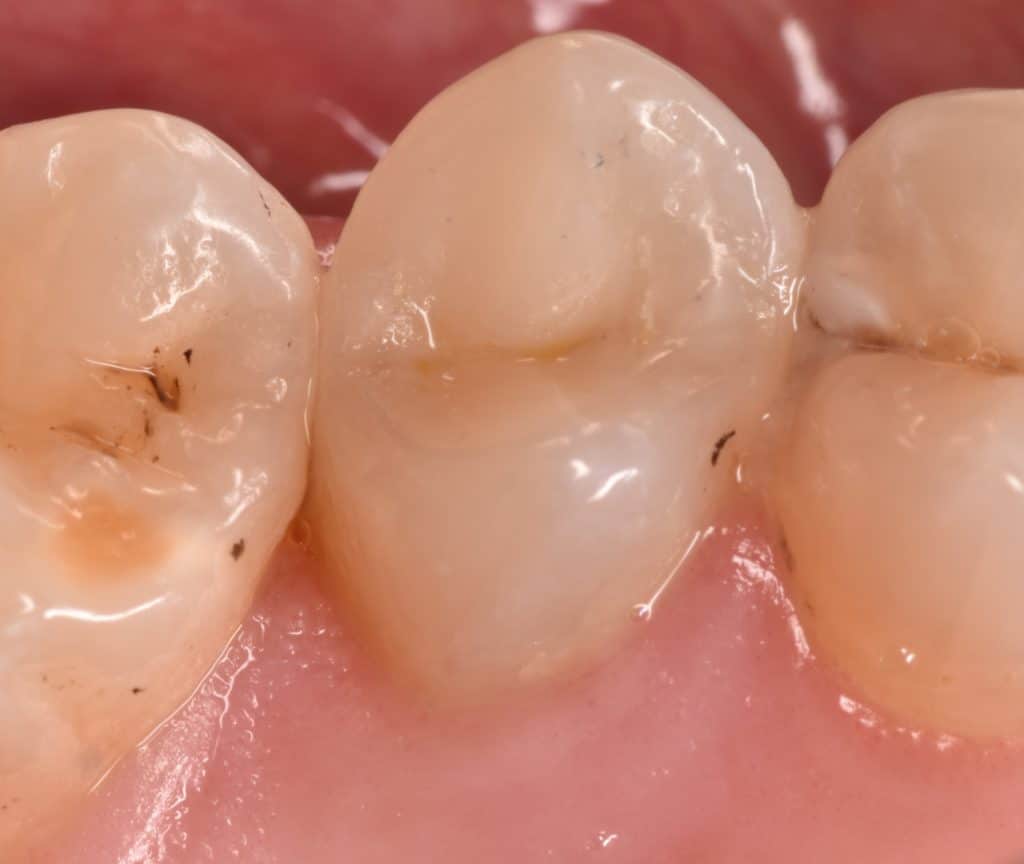

Immediate after rubber dam removal

Waiting for gingival healing

One week later

Look to the gingival healing

Acceptable marginal fitness